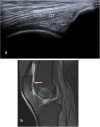

Methods and results: A prospective study was conducted on 143 patients with clinically confirmed AKP. All patients underwent ultrasonography and MRI examinations of the knee. The diagnostic accuracy of ultrasonography compared to MRI for evaluating different findings of possible causes of AKP were analyzed using receiver operating characteristic (ROC) curve and judged by area under curve (AUC). A total of 155 knees were included in the study; 26 knees showed no abnormalities, 19 knees showed positive MRI only, and 110 knees showed positive ultrasonography and MRI. Ultrasonography and MRI reported 11 different findings of possible causes of AKP or related to it. Joint effusion was the most common finding (38%) followed by trochlear cartilage defect (20.6%) and superficial infrapatellar subcutaneous edema (20%). The overall accuracy of ultrasonography was 85.3% sensitivity and 100% specificity. The ultrasonography provided the highest sensitivity (100%) in detecting bipartite patella, followed by 91.5% for joint effusion, and 87.5% for quadriceps tendinopathy. The ROC curve analysis of overall accuracy of ultrasonography showed an AUC of 0.93. The overall Kappa agreement between ultrasonography and MRI was good (k = 0.66).